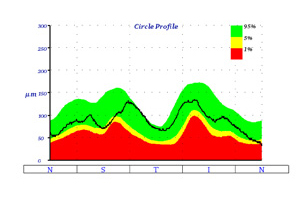

Schwerwiegende Augenerkrankungen wie beispielsweise diabetische Retinopathie, die altersbedingte Makuladegeneration oder das Glaukom kündigen sich häufig durch eine Dickenveränderung der mehrschichtigen Netzhaut an. Einschränkungen des Sehens und merkbare Symptome folgen meist verzögert, wenn das Krankheitsbild bereits fortgeschritten ist. Es ist daher wichtig, dass die Krankheitsbilder in einem möglichst frühen Stadium festgestellt werden.

Mit dem Einsatz der optischen Kohärenztomographie (OCT) gelingt es genaue Informationen über die kleinsten Ebenen im Auge in höchster Qualität und Auflösung zu erhalten. Oft kann diese nicht invasive Methode sogar eine fluoreszenzangiografische Untersuchung ersetzen, bei der ein Farbstoff in die Armvene injiziert wird. Bei manchen unklaren Netzhauterkrankungen, bei denen der Befund einen normalen Augenhintergrund und Fluoreszenzangiographie zeigt, kann erst durch die OCT die richtige Diagnose gestellt werden.

Die Untersuchung am OCT ist ähnlich einem Foto ohne Blitz und dauert nur wenige Minuten. Sie erfolgt absolut schmerzfrei und ohne Berührung der Augen. Die Netzhaut wird in dem untersuchten Bereich durch ein Laserverfahren in optische Schnitte zerlegt und es kann damit wie bei einem mikroskopischen Gewebeschnitt die Netzhaut des Auges beurteilt werden. Die Auflösung der erzeugten Bilder ist ca. 10-mal höher als bei herkömmlichen Ultraschallverfahren am Auge und wesentlich genauer als bei einer Computertomographie (CT) oder einer Magnetresonanztomographie (MRT).

Bei all diesen Vorteilen birgt sie aber den Nachteil, dass diese Untersuchung keine kassenärztliche Leistung ist und somit vom Patienten selbst getragen werden muss. Durch Sparzwänge in unserem Gesundheitssystem ist es z. Zt. fraglich, ob diese Methode in den Leistungskatalog der GKV aufgenommen wird.

Der optische Schnitt einer normalen Netzhaut

Die untere Abbildung zeigt einen Schnitt durch die Netzhautmitte (Makula) mit der wichtigen Stelle für das Scharfsehen - die Sehgrube (Fovea). Die Einsenkung stellt den Normalbefund dar, welches in der dreidimensionalen Bildgebung besonders gut veranschaulicht wird.

normaler Netzhautbefund - OCT

normaler Augenhintergrund

3D Darstellung- OCT

Netzhauterkrankungen, bei denen die Untersuchung einer OCT oft sinnvoll und wertvoll ist:

Optische Kohärenztomographie – OCT

Beispiel: Feuchte altersbedingte Makuladegeneration

68-jähriger Patient mit zunehmender Sehminderung seit 6 Wochen auf 0,3 (30%). Nach 3-maliger Anti-VEGF Therapie Rückgang des Ödems und Besserung auf 0,5

Beispiel: Venöser Gefäßverschluss

58-jähriger Patient mit plötzlicher Sehminderung seit 6 Wochen auf 0,1 (10%). Nach 3-maliger Anti-VEGF Therapie Rückgang des Ödems und Besserung auf 0,63

vor der Behandlung

nach der Behandlung

Nervenfaseranalyse (OCT)

Die Untersuchung am OCT ist ähnlich einem Foto ohne Blitz und dauert nur wenige Minuten. Sie erfolgt absolut schmerzfrei und ohne Berührung der Augen. Die Netzhaut wird um den Sehnerven durch ein Laserverfahren in optische Schnitte zerlegt und es kann damit wie bei einem mikroskopischen Gewebeschnitt die Netzhaut des Auges beurteilt werden. Das OCT führt eine objektive Messung der Nervenfaserschicht durch, da es keine Mitarbeit des Patienten verlangt. Das OCT zeigt frühzeitig ein Glaukom an, sogar wenn das Sehvermögen noch nicht beeinträchtigt ist.

Bei ca. 9-15 monatigen Folgeuntersuchungen kann dann ein Fortschreiten bzw. Stillstand bei entsprechender Therapie festgestellt werden.

Bei allen Vorteilen birgt die Methode aber den Nachteil, dass diese Untersuchung keine kassenärztliche Leistung ist und somit vom Patienten selbst getragen werden muss. Durch Sparzwänge in unserem Gesundheitssystem ist es z. Zt. fraglich, ob diese Methode in den Leistungskatalog der GKV aufgenommen wird.

Ausdruck OCT: normale Papille mit normaler Nervenfaserschicht

Sehnervenfaseranalyse